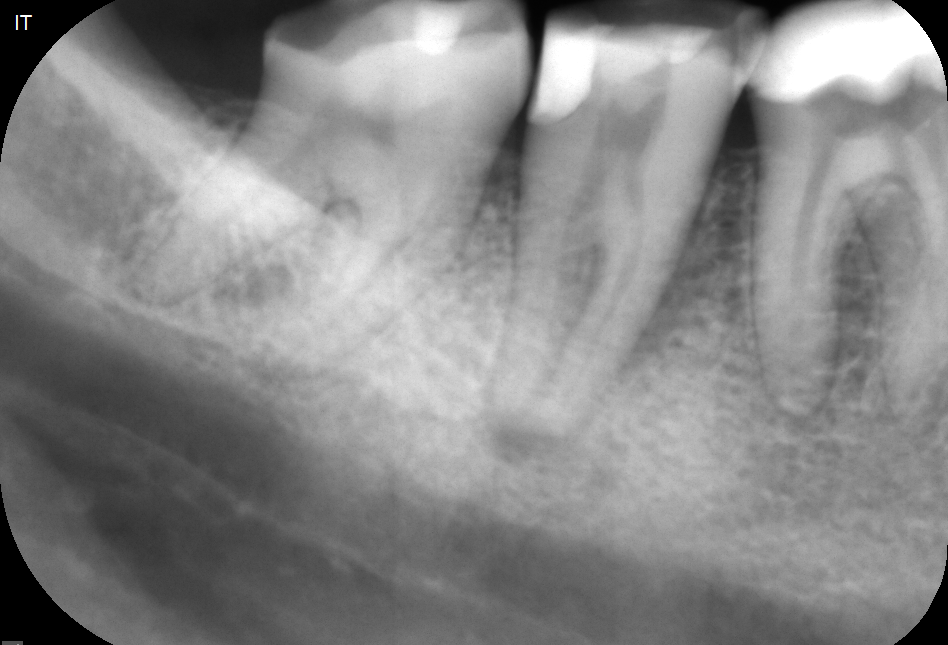

Zobe moramo zdraviti kadar pride do vnetja zobnega živca (pulpe) ali njegovega odmrtja (gangrena). Če kariesa ne odstranimo pravočasno, ta doseže zobni živec. To je lahko za vas popolnoma neboleče in brez težav, običajno pa se kaže s klasičnim zobobolom, ki se po moči lahko meri z najhujšimi telesnimi bolečinami. Zdravljenje zoba ponavadi zahteva več obiskov, ravno pri tem posegu pa je uporaba operativnega dentalnega mikroskopa najpomembnejša. Med zdravljenjem se poslužujemo tudi pomoči rentgenskih posnetkov, v zelo zahtevnih primerih pa tudi CBCT slikanja (cone-beam computed tomography – ali po slovensko – računalniška tomografija).

Granulom je kronično vnetje na koncu korenine zdravljenega ali gangrenoznega zoba. Vnetje povzročajo bakterije, ki so ostale v zobni korenini po zdravljenju. Skoraj 90% vseh granulomov ne povzroča bolečin. Zobozdravniki pa radi označujemo granulome z izrazom “tempirana bomba”. Granulom lahko namreč 10, 20 ali celo več let ne dela težav, počasi raste in topi kost, na enkrat pa izbruhne in vam začne delati ogromne težave. Glavne težave so bolečina, huda oteklina, vročina in splošno slabo počutje.Zato je nujno, da granulome opazimo pravočasno s pomočjo rentgenske diagnostike in jih skušamo s pomočjo endodontskega zdravljenja pozdraviti. Pogosto je ob izbruhu namreč edina rešitev odstranitev (puljenje) zoba.

Mnogo ljudi ima enega ali več zdravljenih zob. Zdravljenje zob je, zaradi komplicirane anatomije (zgradbe) zob, zelo zahtevno. Zato je žalostna resnica, da je večina zob, ki je bila zdravljena pred več kot 10 leti, zdravljena slabo. Take zobe je potrebno rentgensko kontrolirati, in v primeru, da opazimo na koncu korenin kronične spremembe, tudi ponovno zdraviti. Ponovno endodontsko zdravljenje lahko vključuje tudi poseg apikotomije. Če zdravljenje iz določenih razlogov ni možno, ni uspešno, ali pa je napoved izida zelo slaba, svetujemo odstranitev zoba in nadomeščanje z zobnim vsadkom ali mostičkom.